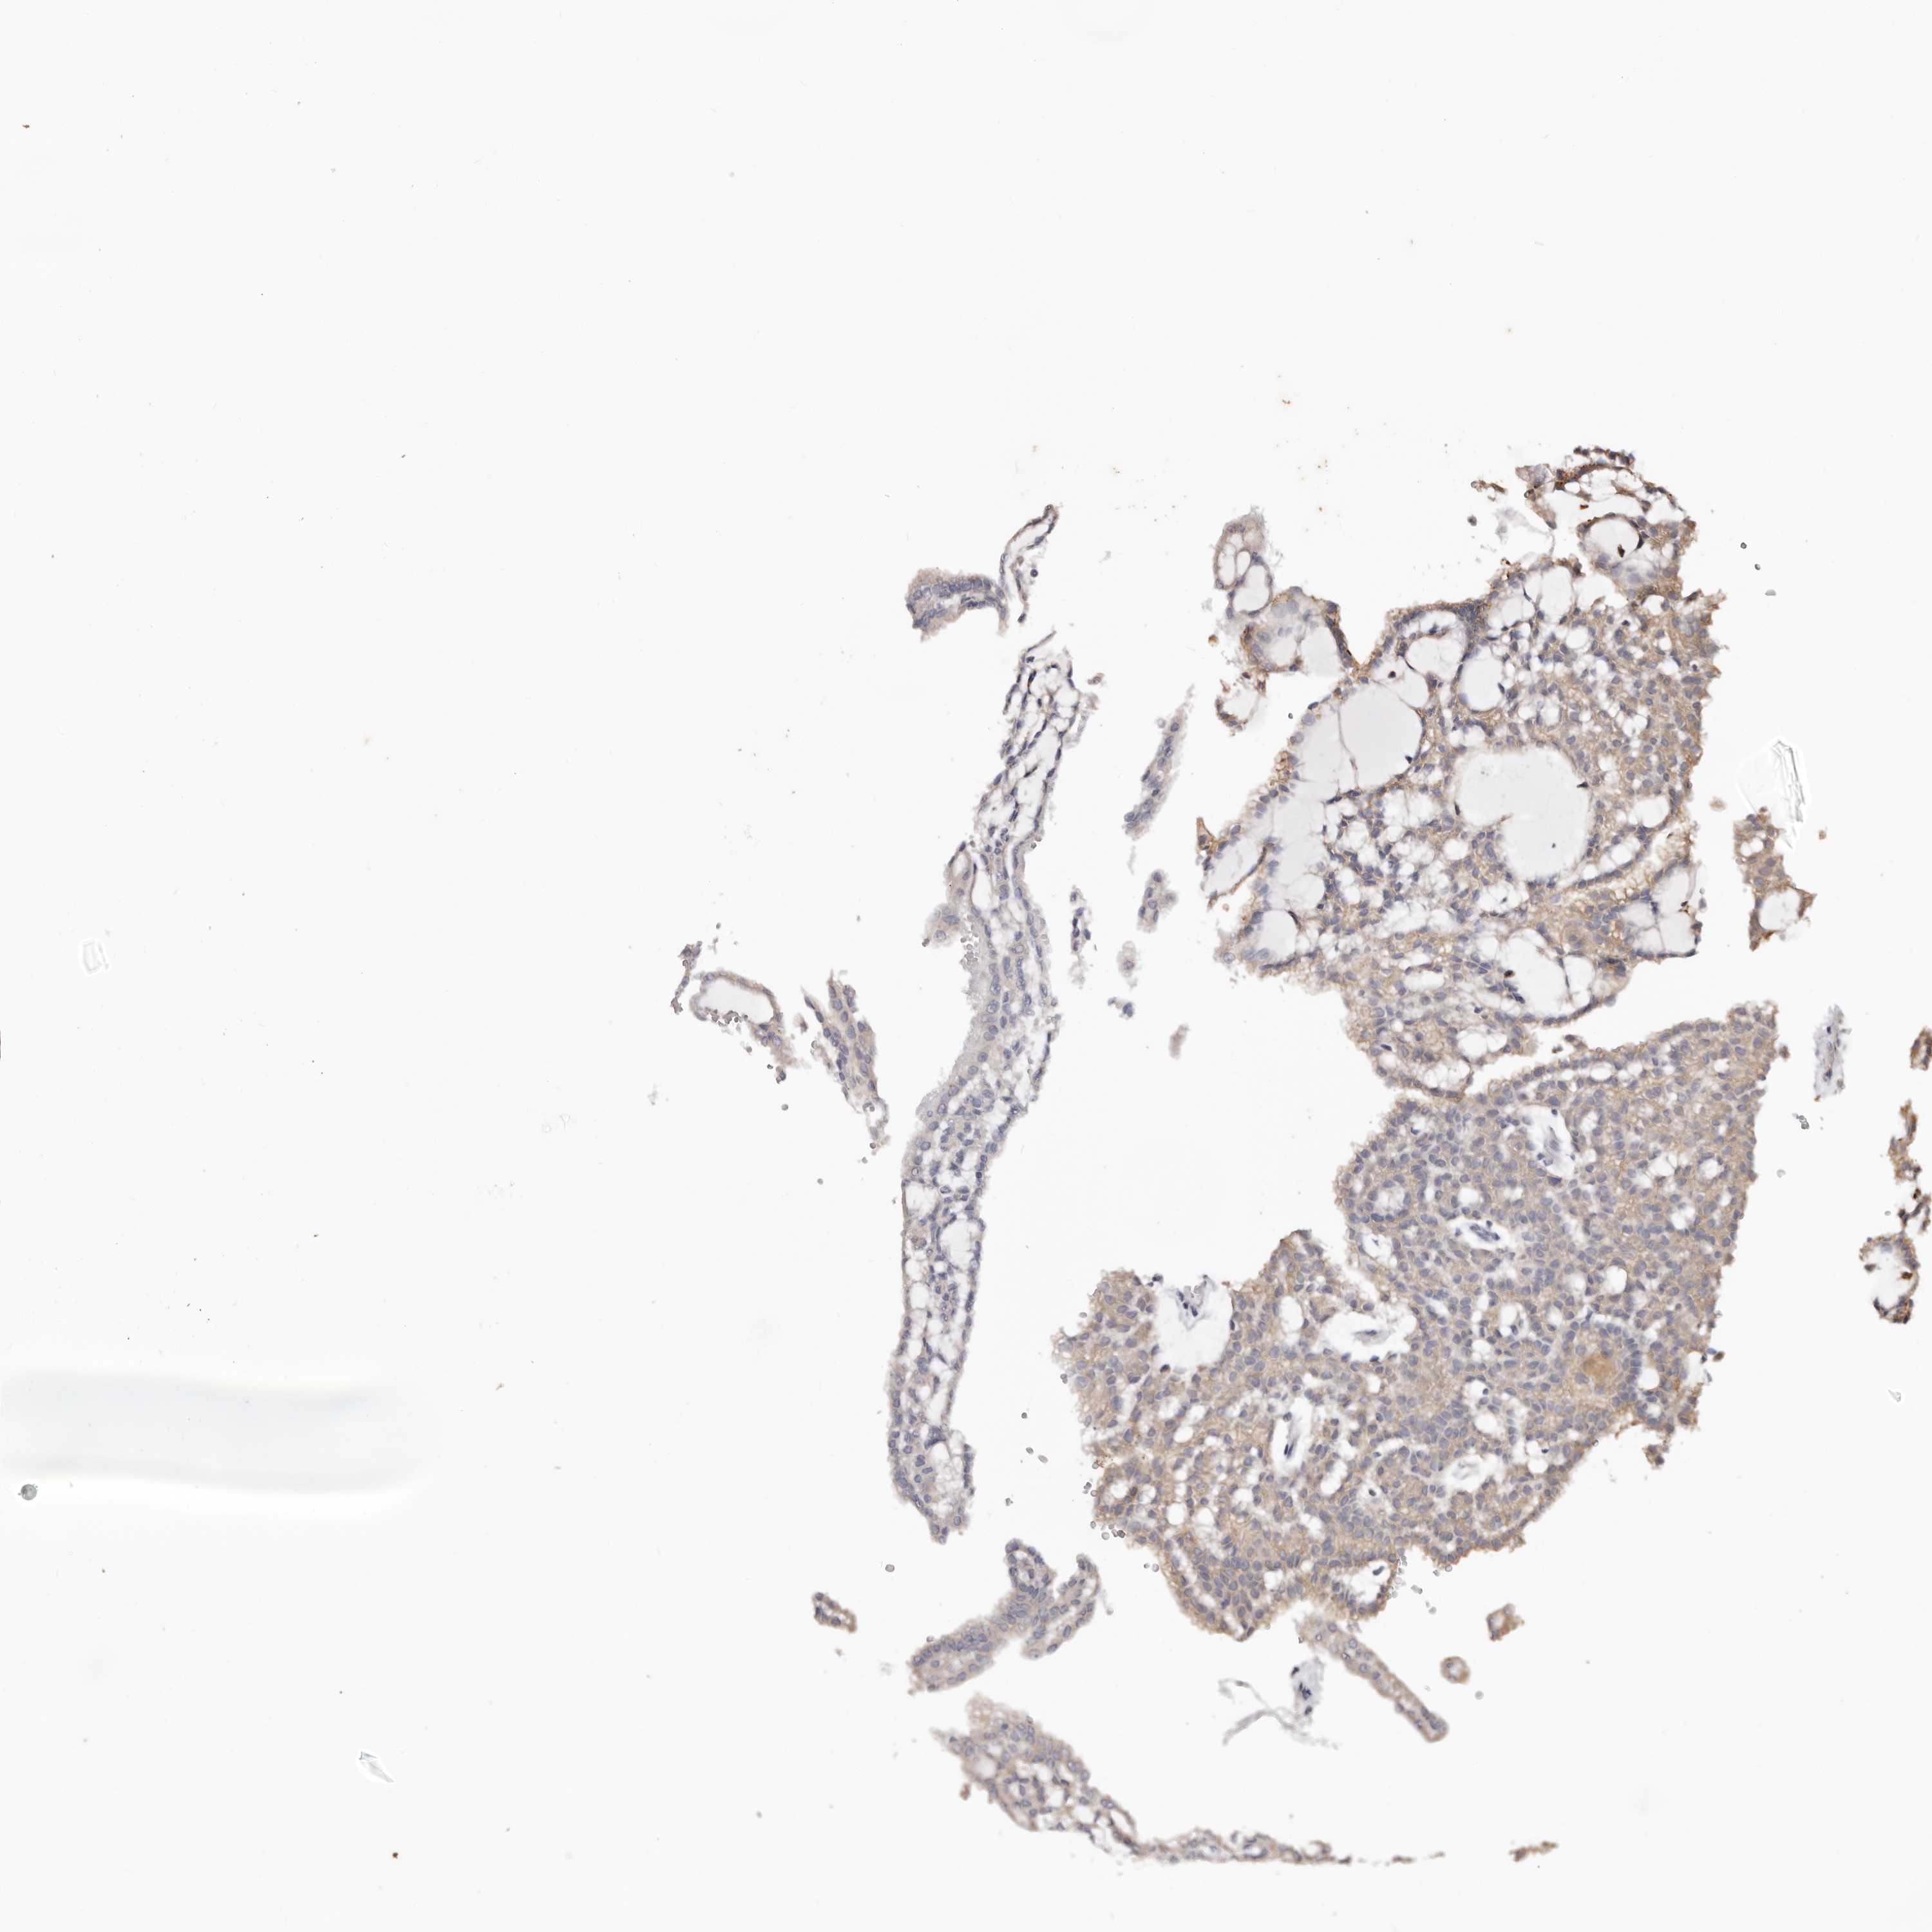

KIDNEY RENAL CLEAR CELL CARCINOMA (VALIDATION) - Interactive survival scatter ploti

The Survival Scatter plot shows the clinical status (i.e. dead or alive) for all individuals in the patient cohort, based on the same data that underlies the corresponding Kaplan-Meier plots. Patients that are alive at last time for follow-up are shown in blue and patients who have died during the study are shown in red.

The x-axis shows the expression levels (FPKM) of the investigated gene in the tumor tissue at the time of diagnosis. The y-axis shows the follow-up time after diagnosis (years). Both axes are complimented with kernel density curves demonstrating the data density over the axes. The top density plot shows the expression levels (FPKM) distribution among dead (red) and alive patients (blue). The right density plot shows the data density of the survived years of dead patients with high and low expression levels respectively, stratified using the cutoff indicated by the vertical dashed line through the Survival Scatter plot. This cutoff is automatically defined based on the FPKM cutoff that minimizes the p-score. The cutoff can be changed by dragging the vertical line or by entering a cutoff value in the square labeled "Current cut-off".

Under the Survival Scatter plot the p-score landscape (black curve; left axis) is shown together with dead median separation (red curve; right axis). Dead median separation is the difference in median mRNA expression between patients who have died with high and low expression, respectively. It is calculated as follows: median FPKM expression of dead patients with high expression - median FPKM expression of dead patients with low expression. This is intended to aid the user in visually exploring custom cutoffs and the associated p-scores and dead median separation.

Individual patient data is displayed and can be filtered by clicking on one or more of the category buttons on the top of the page. Categories describing expression level and patient information include: high, low, alive, dead, female, male and tumor stages. The scale of the x-axis can be toggled between linear and log-scale by clicking on the "x log" button. Mouse-over function shows TCGA ID, patient information and mRNA expression (FPKM) for each patient.

& Survival analysisi

Kaplan-Meier plots summarize results from analysis of correlation between mRNA expression level and patient survival. Patients were divided based on level of expression into one of the two groups "low" (under cut off) or "high" (over cut off). X-axis shows time for survival (years) and y-axis shows the probability of survival, where 1.0 corresponds to 100 percent.

TYW3 is not prognostic in Kidney Renal Clear Cell Carcinoma (validation)

Best expression cut offi

Based on the FPKM value of each gene, patients were classified into two groups and association between prognosis (survival) and gene expression (FPKM) was examined. The best expression cut-off refers the FPKM value that yields maximal difference with regard to survival between the two groups at the lowest log-rank P-value. Best expression cut-off was selected based on survival analysis .

When clicking on this number, the vertical dashed line indicating cut-off, the interactive survival plot, and the Kaplan-Meier curve will be adjusted to show results based on the best expression cut-off.

: 14.59

Median expressioni

Median expression refers to the median FPKM value calculated based on the gene expression (FPKM) data from all patients in this dataset. When clicking on this number, the vertical dashed line indicating cut-off, the interactive survival plot, and the Kaplan-Meier curve will be adjusted to show results based on the median expression.

: N/A

Median follow up timei

Median follow up time refers to the median time (years) after diagnosis with this type of cancer, based on clinical data from all patients in this dataset.

P scorei

Log-rank P value for Kaplan-Meier plot showing results from analysis of correlation between mRNA expression level and patient survival.

N/A

5-year survival highi

5-year survival for patients with higher expression than the expression cutoff.

For melanoma and glioma, 3-year survival is shown.

5-year survival lowi

5-year survival for patients with lower expression than the expression cutoff.

TCGA RNA samplesi

RNA-seq data is reported as average FPKM (number Fragments Per Kilobase of exon per Million reads), generated by the The Cancer Genome Atlas (TCGA) .

Normal distribution across the dataset is visualized with box plots, shown as median and 25th and 75th percentiles. Points are displayed as outliers if they are above or below 1.5 times the interquartile range. FPKM values of the individual samples are presented next to the box plot.

Average pTPM 16.7

Number of samples 100